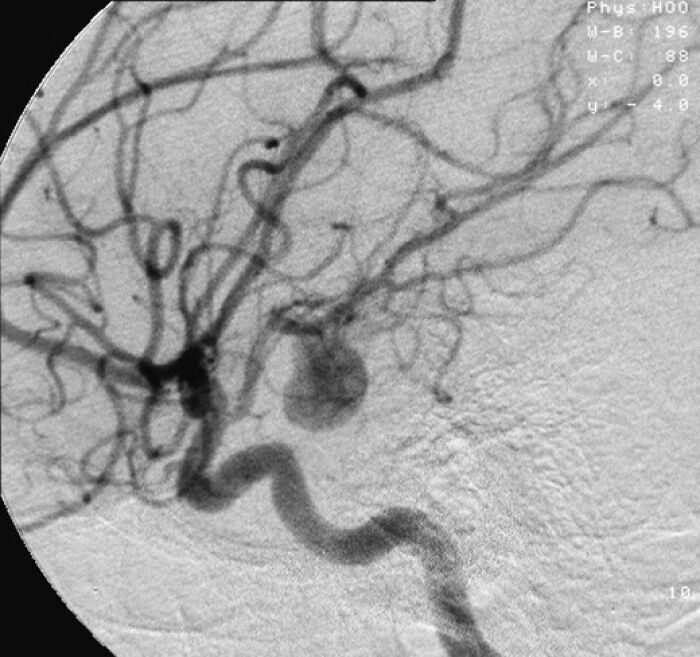

Sudden aneurysms are pretty scary.

PapaTua:

My sister passed away this way right in front of me.

She had a mild headache all day, then a sharper pain for about 30 seconds, and then gone.

I'll be the same age she was when she passed in a year or two. I hope to go the same way at the same age.